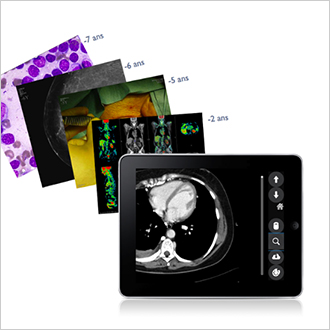

TM-Publisher Web

Informationen müssen überall verfügbar sein, unabhängig vom Aufenthaltsort der Person. Das Gleiche gilt für die Bilddiagnostik: Die Untersuchung des Patienten ist durchgeführt worden, und der behandelnde Arzt muss die Ergebnisse ohne Verzögerung sehen können, unabhängig davon, ob er sich im Krankenhaus oder in einer Praxis ausserhalb des Krankenhauses befindet. Genau dies ist die Philosophie von TM-Publisher Web: den Zugang zu Bildern von jedem an das Internet angeschlossenen Computer aus zu ermöglichen und gleichzeitig die Vertraulichkeit der Patientendaten zu gewährleisten.

TM-Community

TM-Community ist eine cloudbasierte Lösung, mit der Krankenhaus-Sites medizinische Dateien miteinander austauschen können. Es können Dokumente in allen Formaten (PDF, DICOM, JPEG usw.) ausgetauscht werden, und sie sind dabei geschützt und nachverfolgbar. Diese Lösung macht es unter anderem möglich, eine zweite Diagnosemeinung anzufordern, eine Datei an ein Spezialzentrum zu senden oder Bilder täglich an ein Überweisungszentrum zu senden.